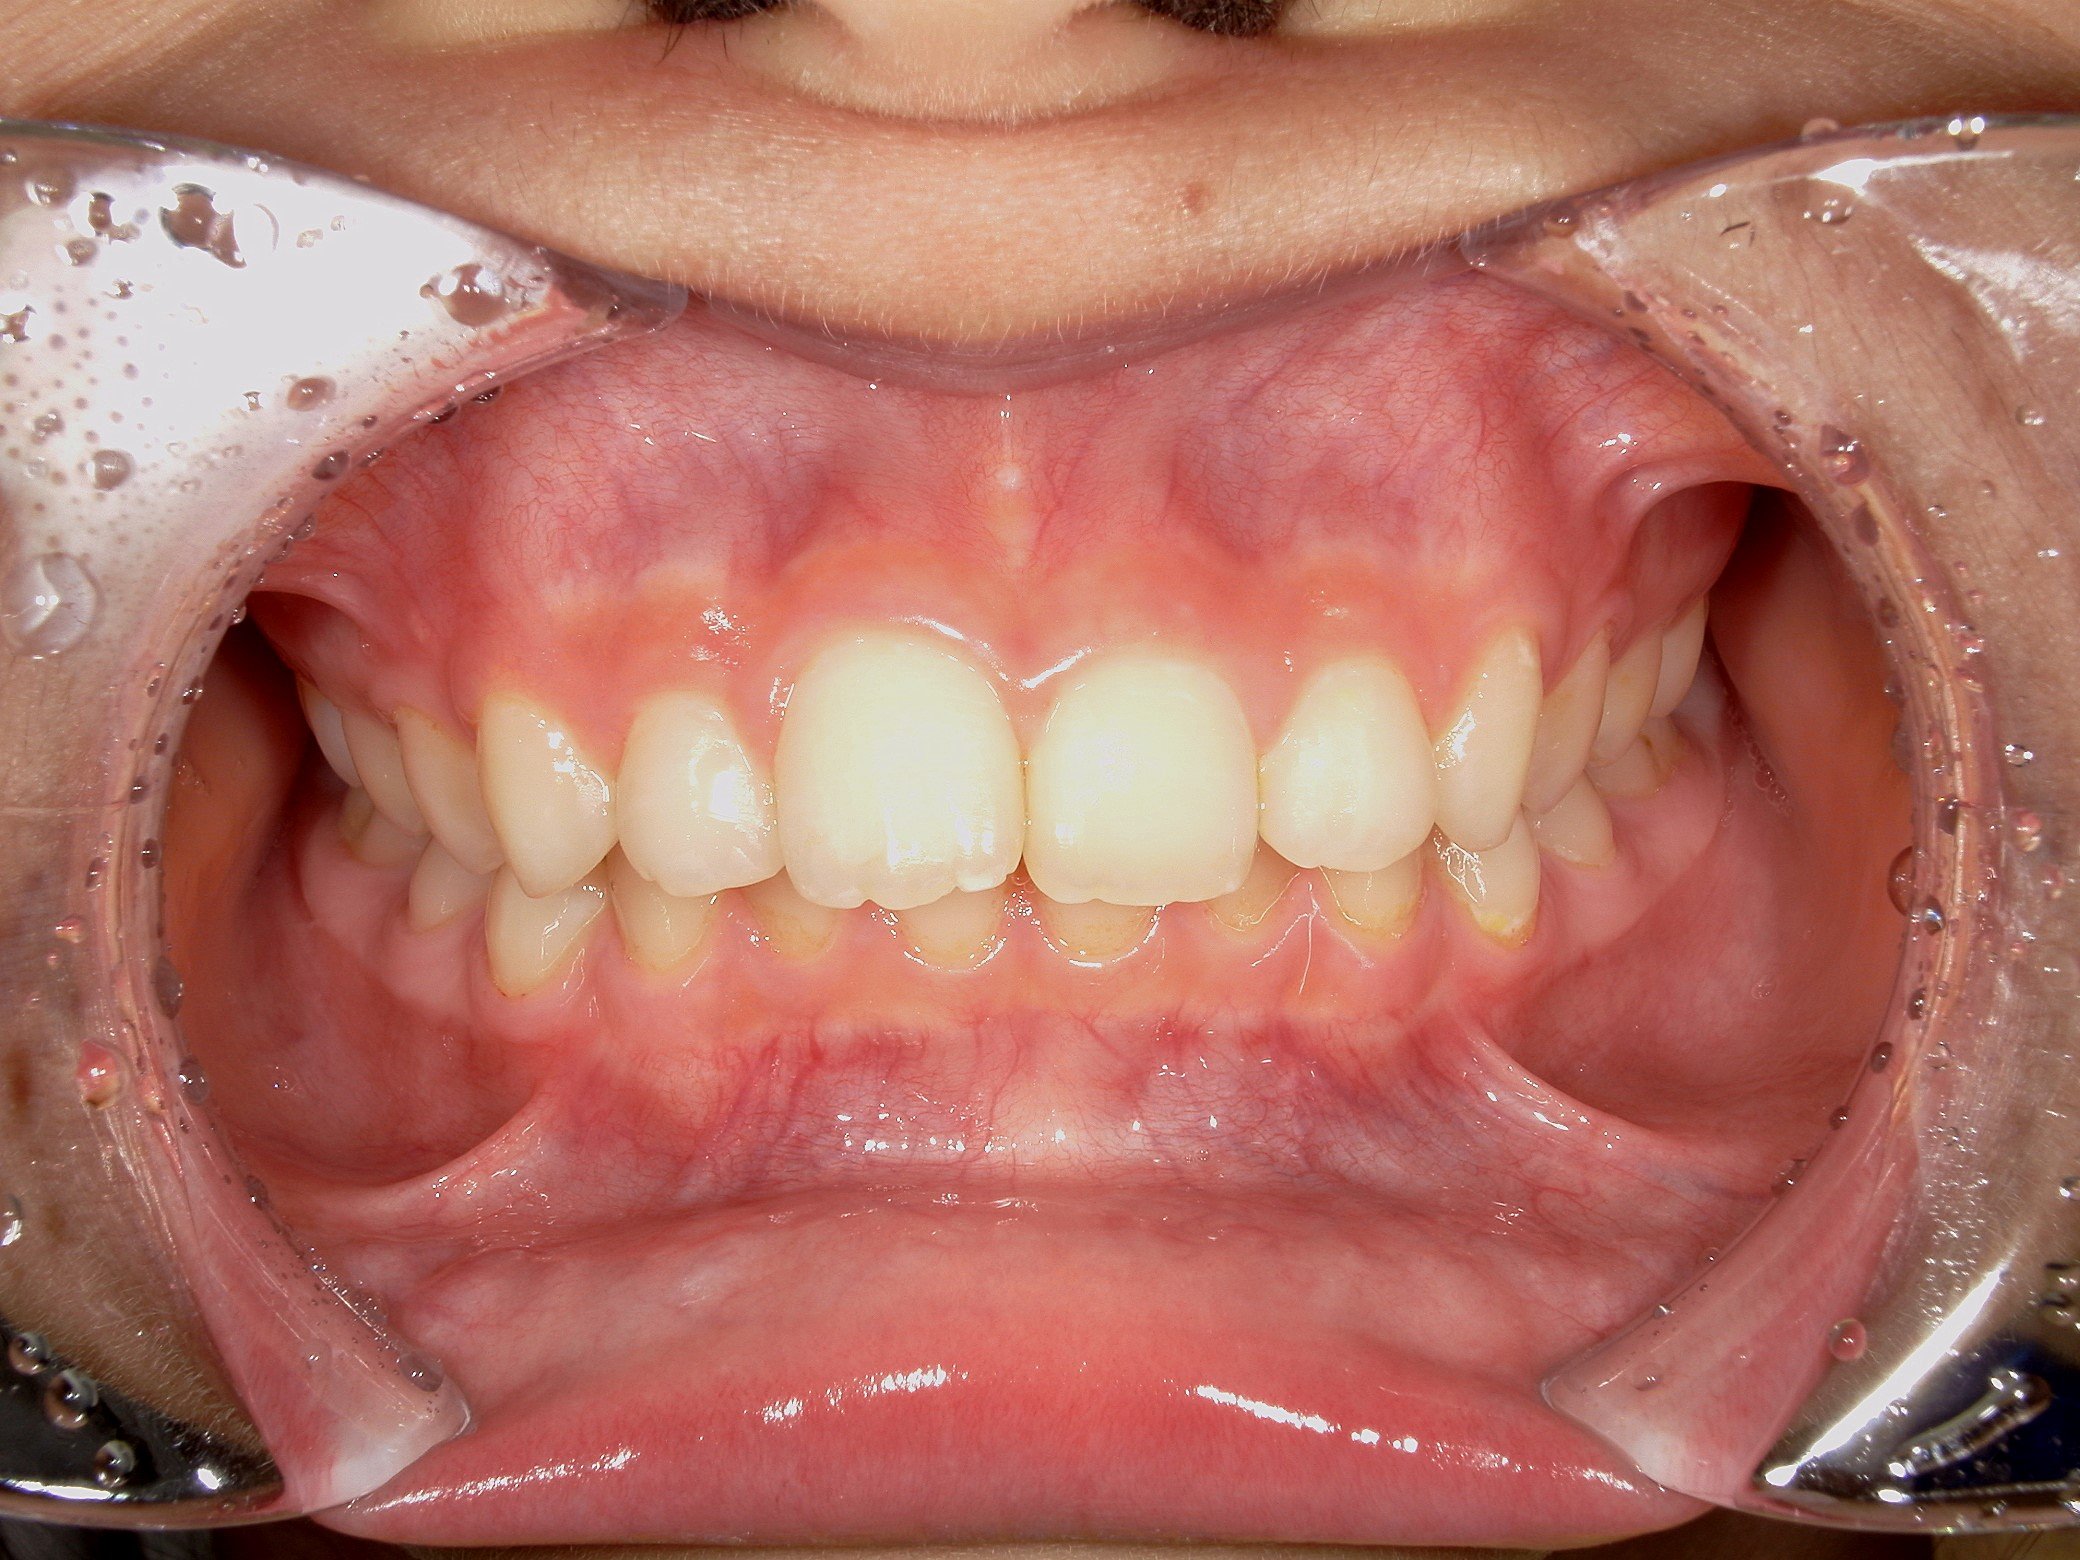

歯系: 前歯の前後的な差が著しく大きい「著大なオーバージェット」と、下の前歯が上の前歯に深く隠れてしまう「過蓋咬合(かがいこうごう)」が認められました。

大きな問題点: 本来なら生えきっているはずの下顎左右の第二大臼歯(一番奥の7番目の歯)が、萌出時期を過ぎても歯ぐきに埋まったままの「半萌出状態」となっていました。

・著大だったオーバージェット(前歯の突出)が完全に解消され、良好な被蓋関係(咬み合わせ)を獲得しました。